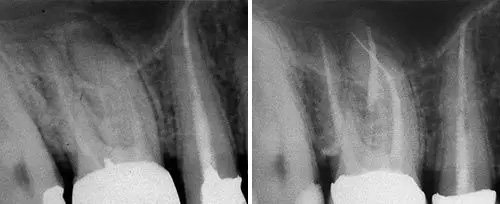

Endodontic Treatment